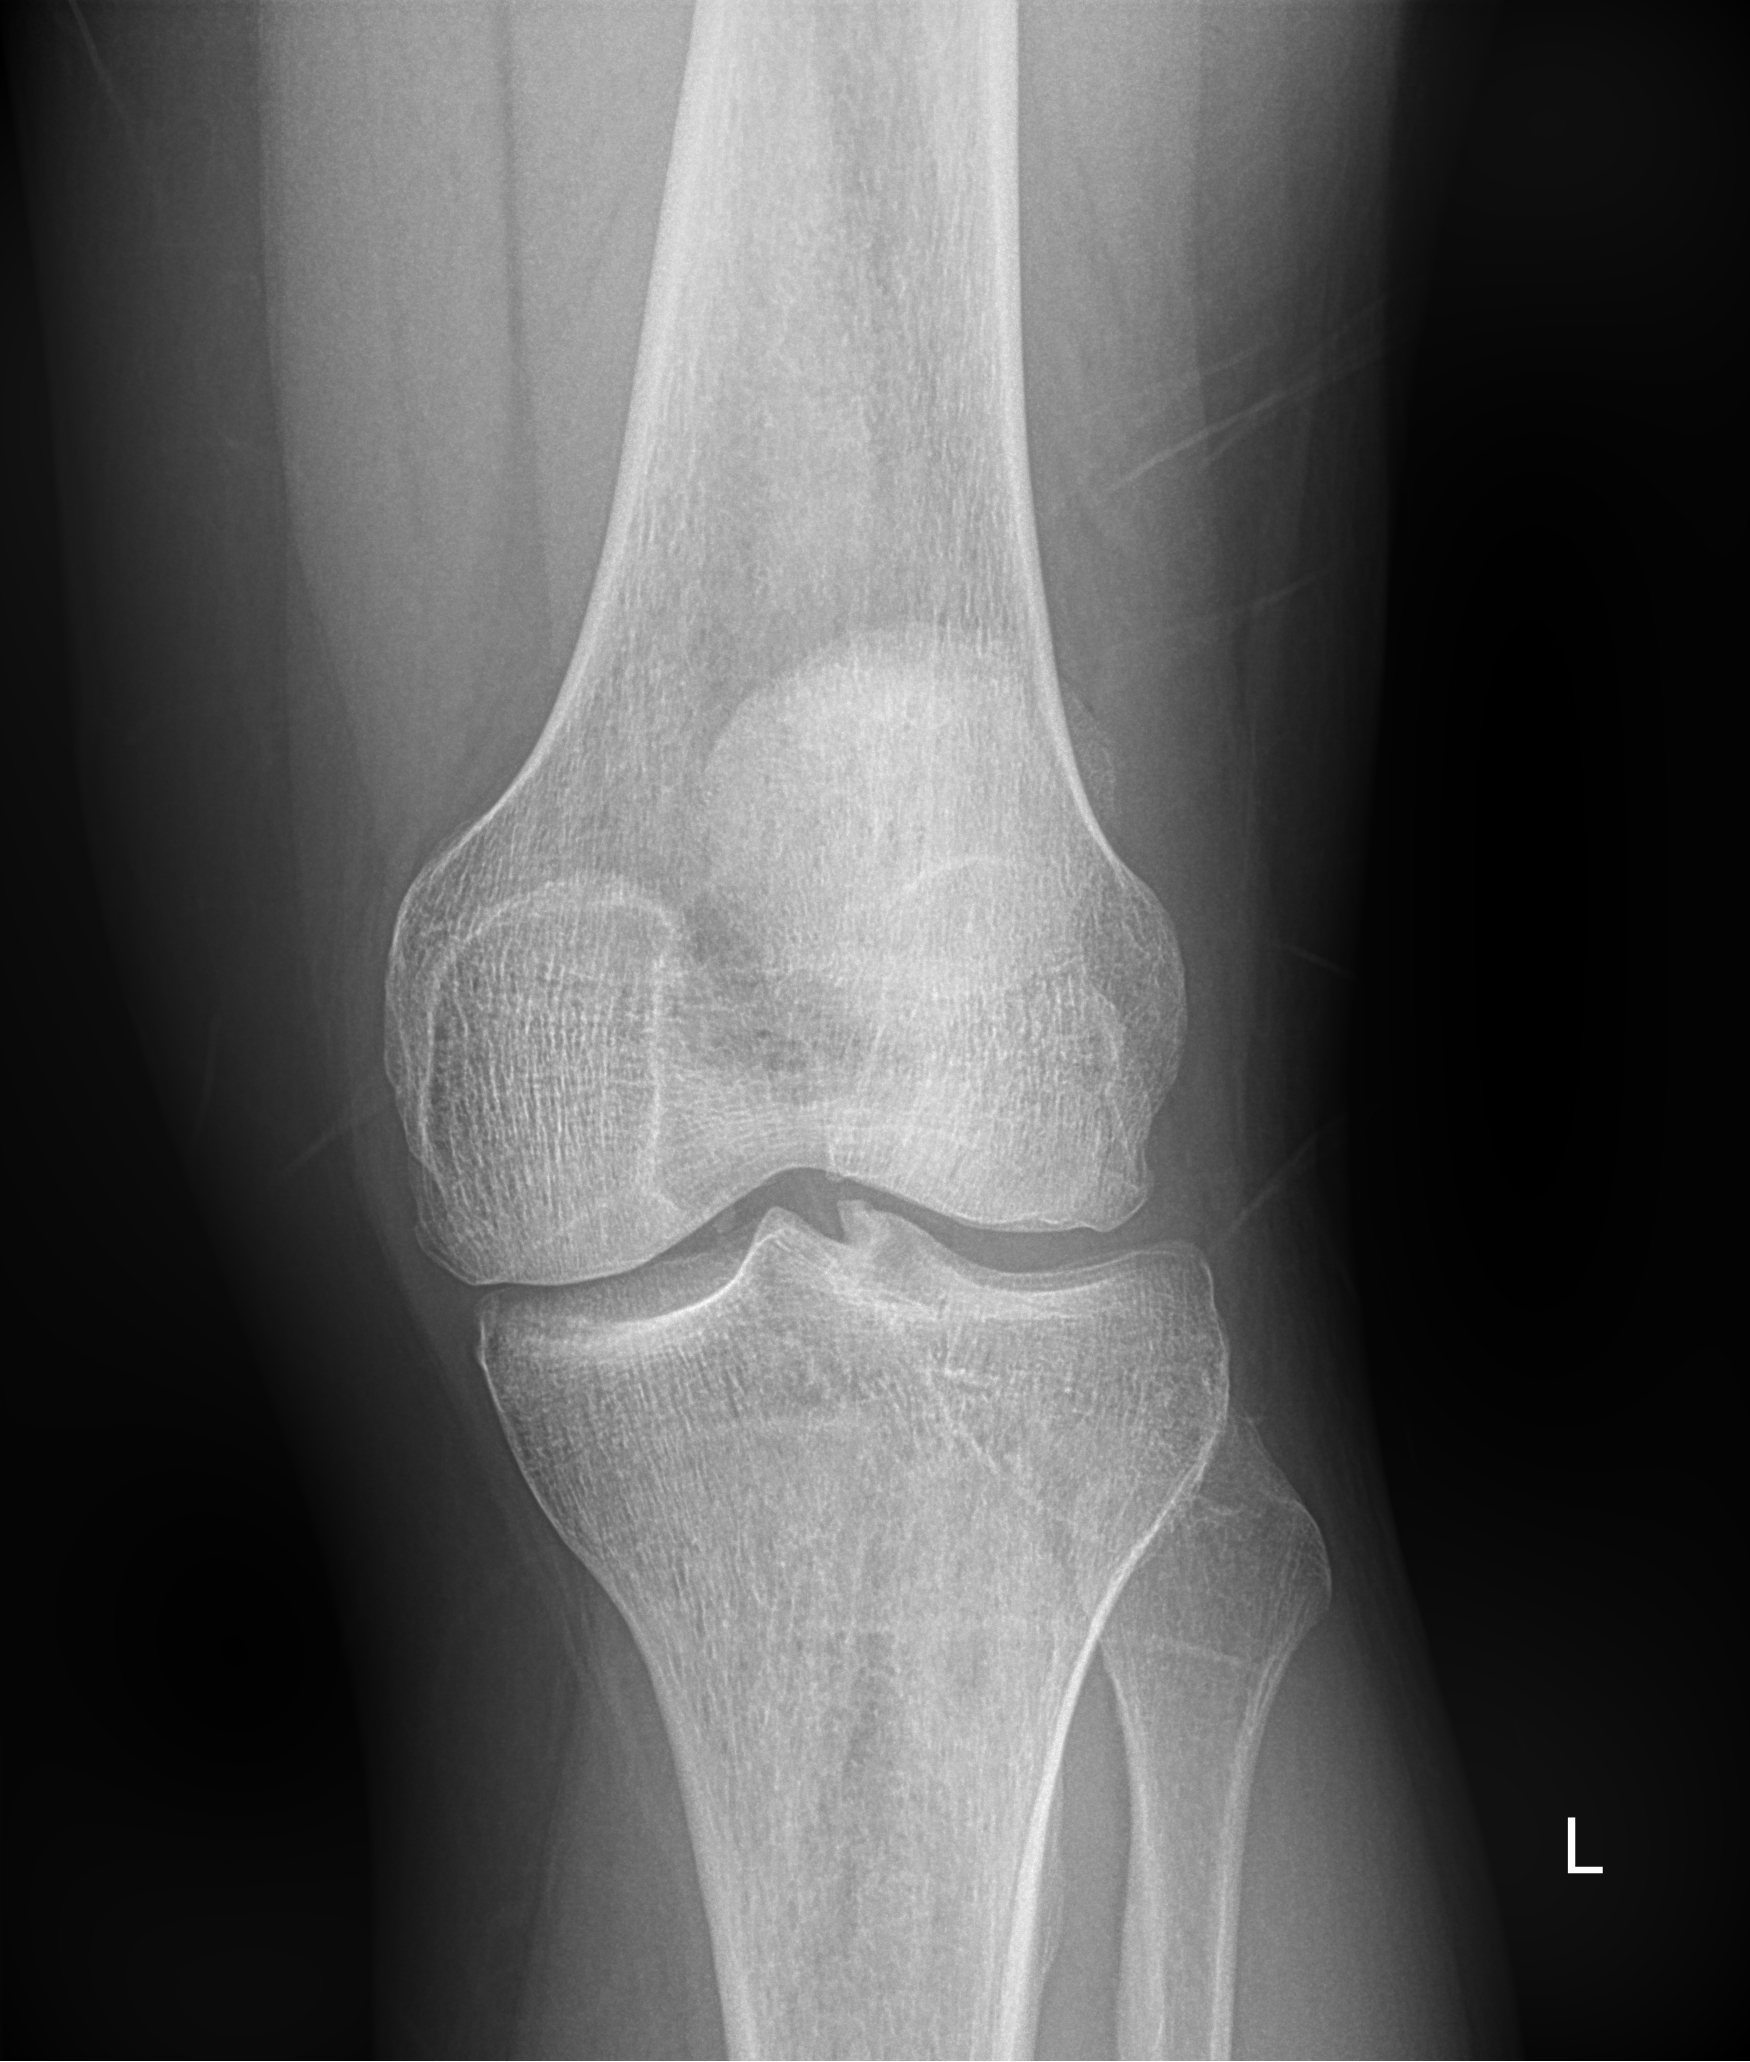

-коленный сустав (травмы мениска, переломы, изменений в кости и суставе);